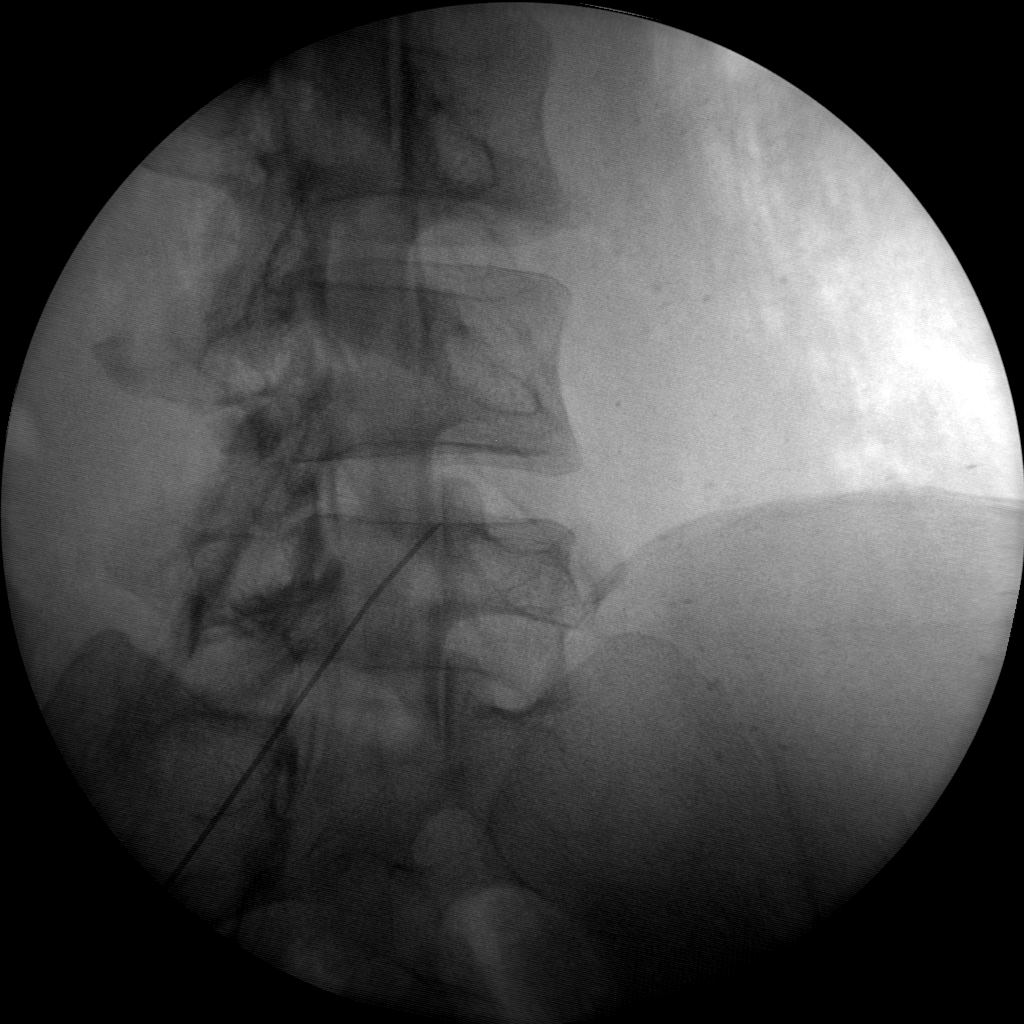

Versatility

Skan-C is a highly versatile machine that can be used for a variety of pain management treatments, including epidural injections, nerve blocks, joint injections, and more.

Ease of use

Skan-C provides 45 degree over rotation (over scan) that is particularly helpful for pain management applications. Skan-C is designed to be user-friendly, with an intuitive interface that allows doctors to quickly and easily adjust settings and customize imaging parameters.